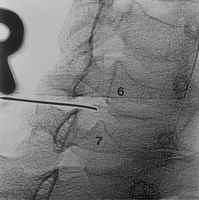

Distinguiamo tra i trattamenti chirurgici quelli

effettuati in artroscopia: da quelli eseguiti a

cielo aperto: i primi comprendono il lavaggio

articolare ,la pulizia con shaving cartilagineo

ed offrono un beneficio a medio termine con una

minima morbilita. Altri trattamenti

artroscopici quali la condroplastica, le

microfratture od i trapianti di cartilagine

richiedono un periodo di scarico articolare ed

una attenta e lunga riabilitazione.